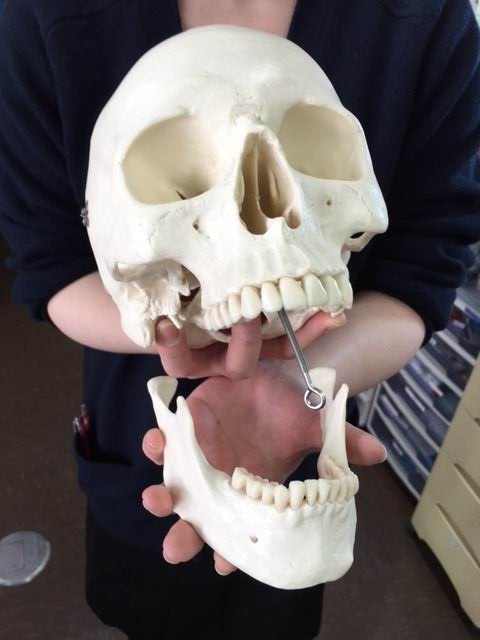

※これはある患者さんの骨の模型です。右上に穴が空いている部分があります。

頭蓋骨をご覧頂くともっとよくわかりますね。

鼻とお口はこうして

繋がっているんです。

※これはある患者さんの骨の模型です。右上に穴が空いている部分があります。